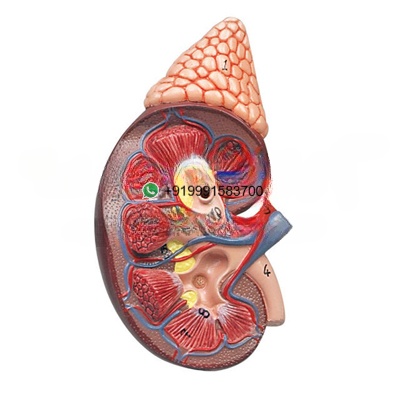

Kidney with Adrenal Gland Anatomy Model for Biology Lab

Kidney with Adrenal Gland Anatomy Model Manufacturer, Supplier and Exporter for Biology Lab – Life size model, 2 parts model of the kidney with the adrenal gland. The model is sectioned along the front plane; showing internal structures, including the

We are leading manufacturers, suppliers & exporters of Kidney with Adrenal Gland Anatomy Model for Biology Lab. to get high quality designed Kidney with Adrenal Gland Anatomy Model for Biology Lab and Lab Education & Training Products for schools, colleges, TVET, universities, training laboratory, research lab, hospital and medical lab and various Industrial Laboratory Training Program. We accept bulk orders for government tenders in all countries around the globe.